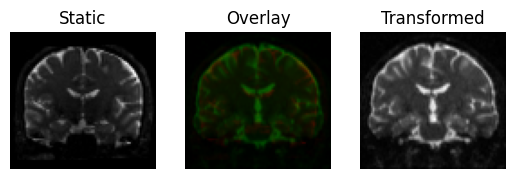

This produces a slight rotation, and the images are now better aligned

transformed = rigid.transform(moving)

<Figure size 640x480 with 3 Axes>

Registration result with a rigid transform, using Mutual Information.